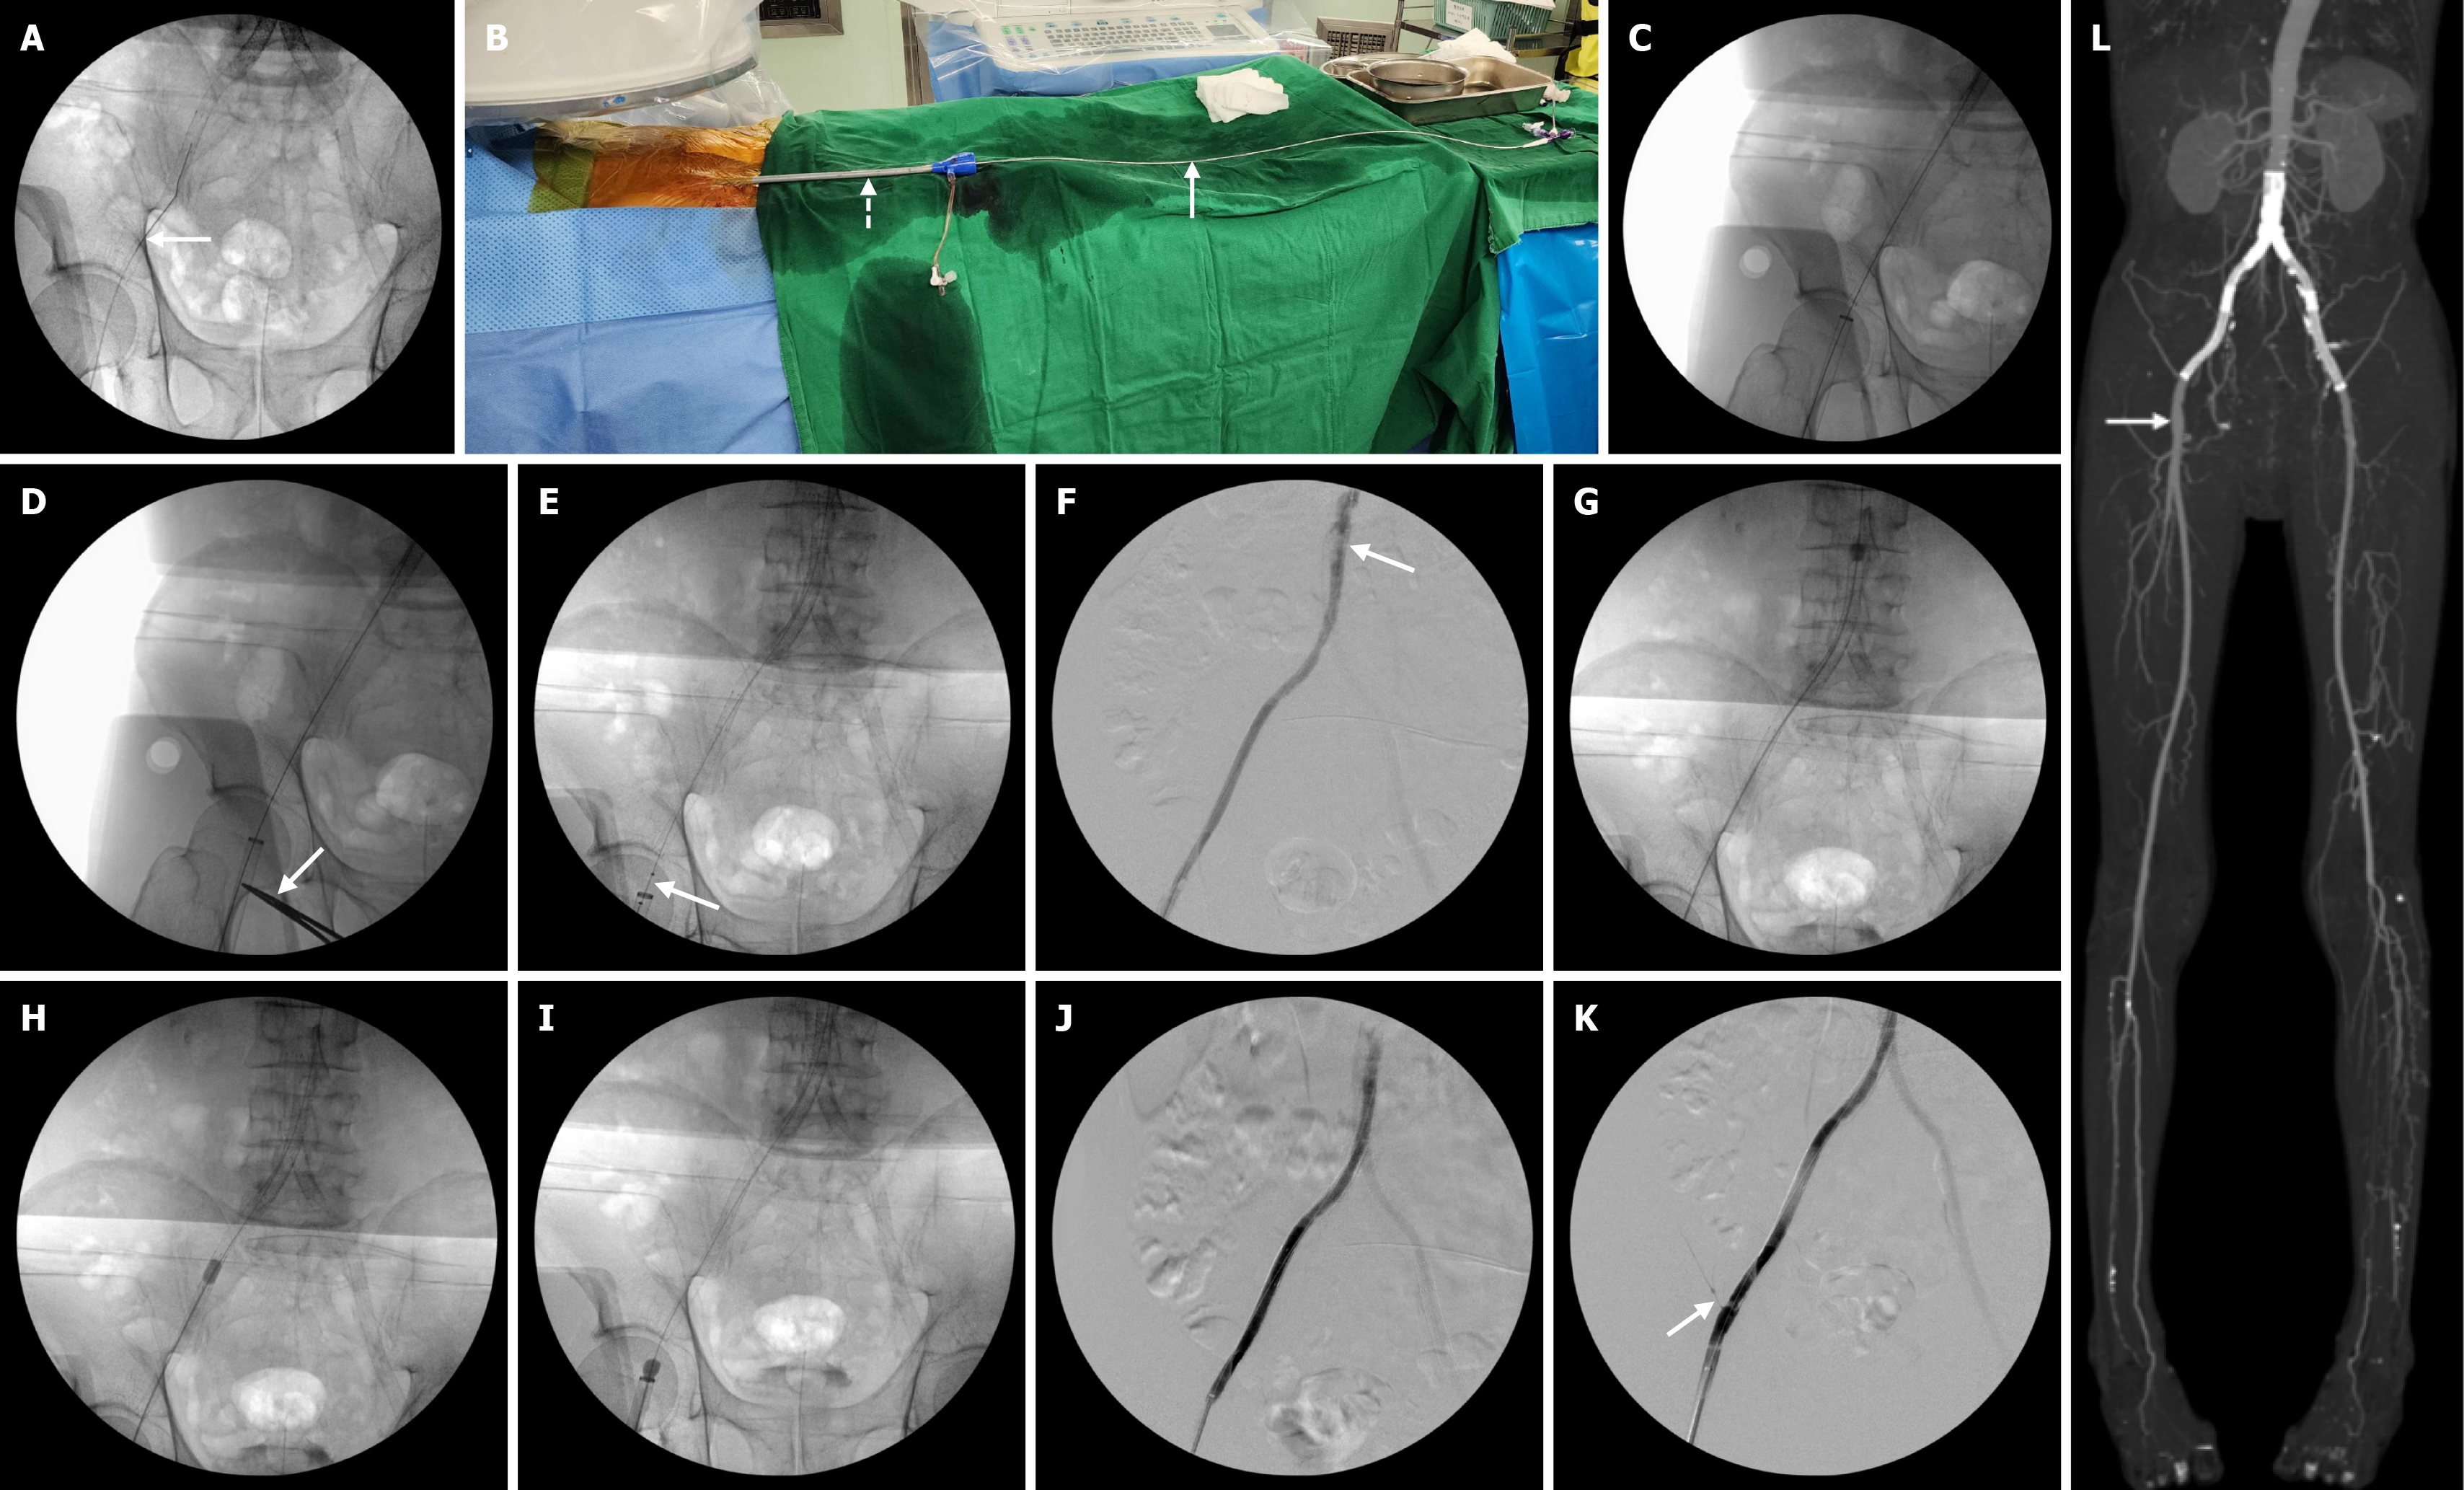

Under general anesthesia, the right common femoral artery was accessed using a micropuncture set under ultrasound guidance. An 035In straight-tip Terumo guidewire (Terumo Corporation, Japan) was inserted through the right common femoral artery (Figure 2A). After successful access, two 6F Proglides (Abbott Vascular, IL, United States) were applied for future closure using a preclose technique. Then, a 22 French Sentrant introducer sheath (Medtronic, Minneapolis, MN, United States) was inserted into the right common femoral artery to prevent distal embolization during the procedure. Then, an Angiojet Omni thrombectomy catheter (Boston Scientific, Marlborough, MA, United States) was introduced through this sheath (Figure 2B). Just before the thrombectomy, a fluoroscopic image showed the successful guidewire passage and placement of a large bore sheath (Figure 2C). A mosquito clamp was placed onto the access site (Figure 2D). It could be helpful to avoid the inadvertent pullout of a large bore sheath during the procedure. Aspirational thrombectomy was performed using an Angiojet Omni thrombectomy catheter in a retrograde fashion from the proximal portion of the abdominal stent down to the distal portion of the right iliac stenting (Figure 2E). After the aspiration thrombectomy, the angiogram demonstrated a nearly complete thrombectomy and residual organized thrombus at the proximal stent portion (Figure 2F). Conventional mechanical thrombectomy was done using a 5.5 Fr over-the-wire Fogarty catheter (Edwards Lifesciences, Irvine, CA, United States) from the proximal portion of the stent to the tip of the sheath (Figure 2G-I). Eventually, the organized thrombus was collected in the large bore sheath. Both aspiration thrombectomy and conventional mechanical thrombectomy were performed slowly and gently (see Video). The completion angiogram showed the complete removal of the thrombus and patent stenting site including the right circumflex iliac artery (Figure 2J and K). Postoperative MIP CT image showed no evidence of distal embolization and access site complication as well (Figure 2L).

After the procedure, the right-side ABI was increased to 1.06. Postoperative CT image showed no evidence of distal embolization and any access site complication (Figure 2L). In the postoperative one year, the stenting site was patent.

One limitation of this system is that the organized thrombus cannot be removed. In this case, we could observe that the organized thrombus at the proximal portion of the stent was not removed after the use of this system. For the removal of this organized thrombus, 0.018″ wires are inserted through the stenting portion of the iliac artery to the abdominal aorta. And 5.5Fr over-the-wire Fogarty catheter is advanced, inflated, and pulled back to the sheath. This gentle procedure could be able to completely remove the organized thrombus.

During both aspiration thrombectomy and mechanical thrombectomy, distal embolization is a possible complication. The placement of an embolic protection device could not be used in this approach. Therefore, we used a large diameter sheath similar to the diameter of a native artery. This sheath has frequently been used for endovascular repair of abdominal aortic aneurysms or transfemoral aortic valve implantation[10]. In particular, during the mechanical thrombectomy using an over-the-wire Fogarty catheter, the balloon was inflated and pulled to the sheath to collect the thrombus inside the sheath without distal embolization. The preclose technique has commonly been used for percutaneous femoral closure after large sheath access[11]. Before the insertion of a large diameter sheath, two Proglide™ suture devices were applied. Eventually, we completed the procedure with total percutaneous application.